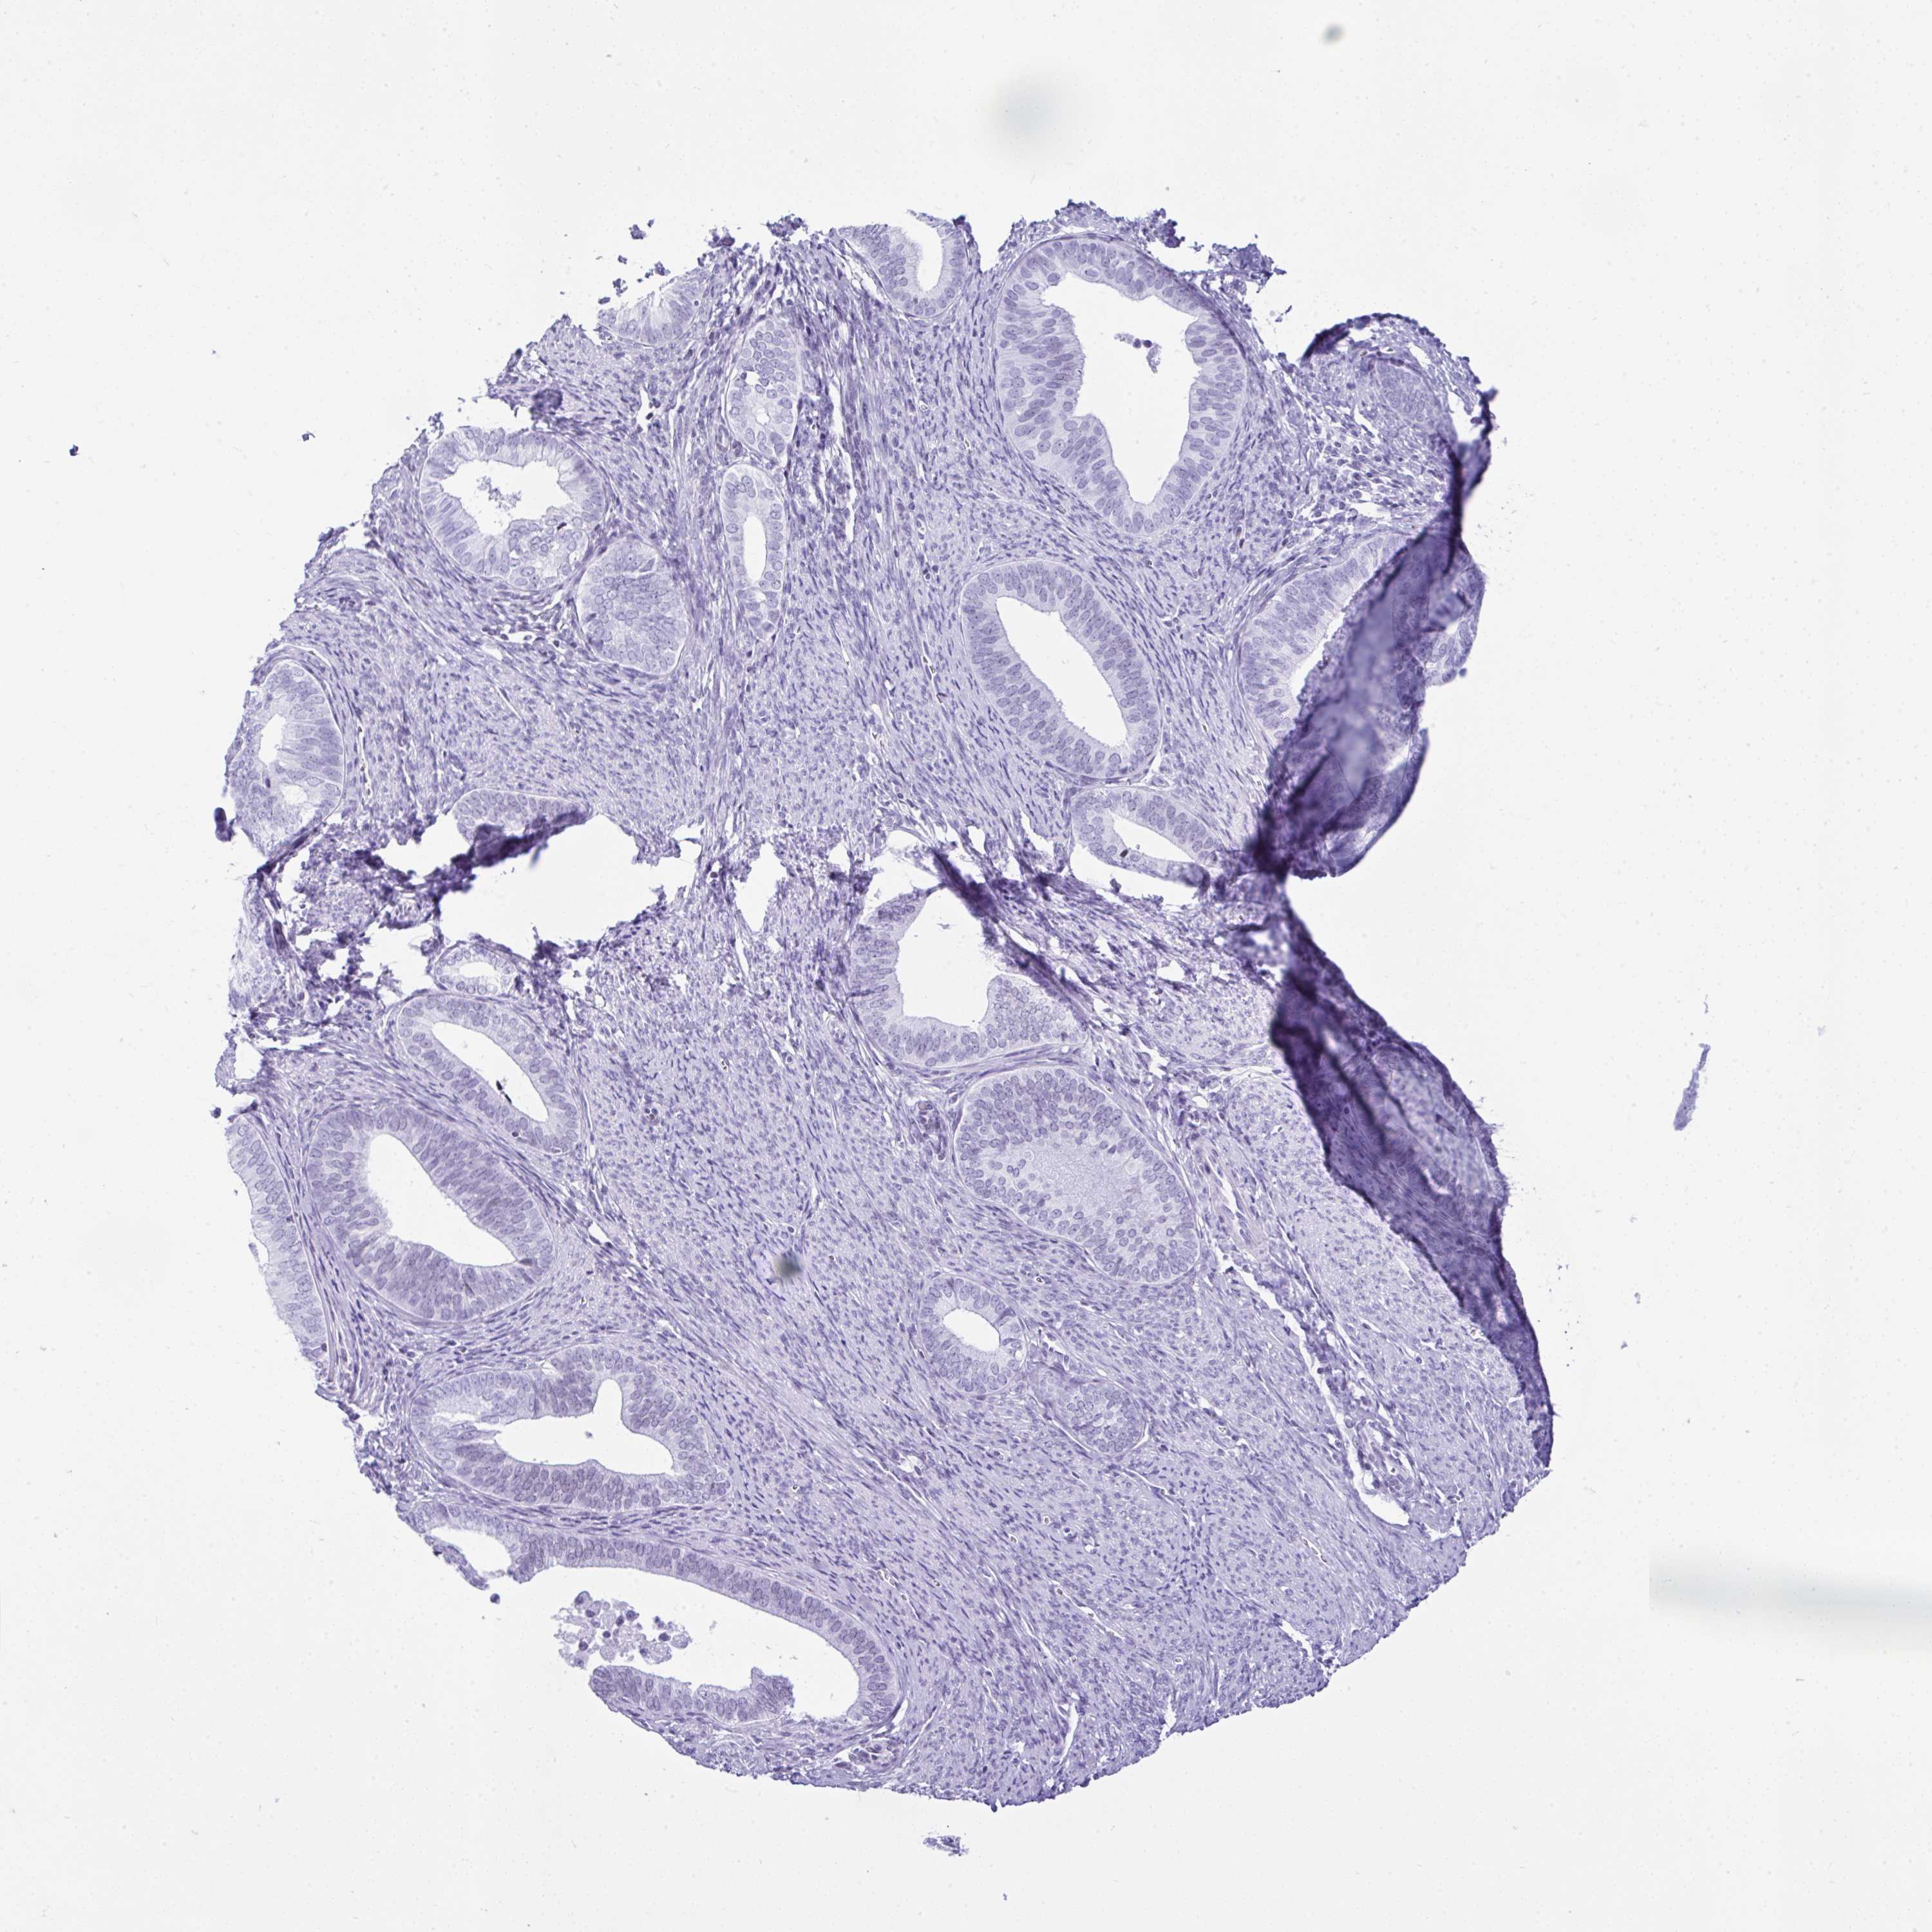

ENDOMETRIAL CANCER - Protein expressioni

A mouse-over function shows sample information and annotation data. Click on an image to view it in a full screen mode. Samples can be filtered based on level of antibody staining by selecting one or several of the following categories: high, medium, low and not detected. The assay and annotation is described here.

Note that samples used for immunohistochemistry by the Human Protein Atlas do not correspond to samples in the TCGA dataset.

Antibody stainingi

Antibody staining in the annotated cell types in the current human tissue is reported as not detected, low, medium, or high, based on conventional immunohistochemistry profiling in selected tissues. This score is based on the combination of the staining intensity and fraction of stained cells.

Each image is clickable and will lead to virtual microscopy that enables deeper exploration of all samples and also displays staining intensity scores, fraction scores and subcellular localization as well as patient and tissue information for each sample.

Antibody HPA055114

Staining

High

Medium

Low

Not detected

Intensity

Strong

Moderate

Weak

Negative

Quantity

>75%

75%-25%

<25%

None

Location

Nuclear

Cytoplasmic/membranous

Cytoplasmic/membranous,nuclear

Adenocarcinoma, NOS

Carcinoma, NOS

Adenocarcinoma, metastatic, NOS